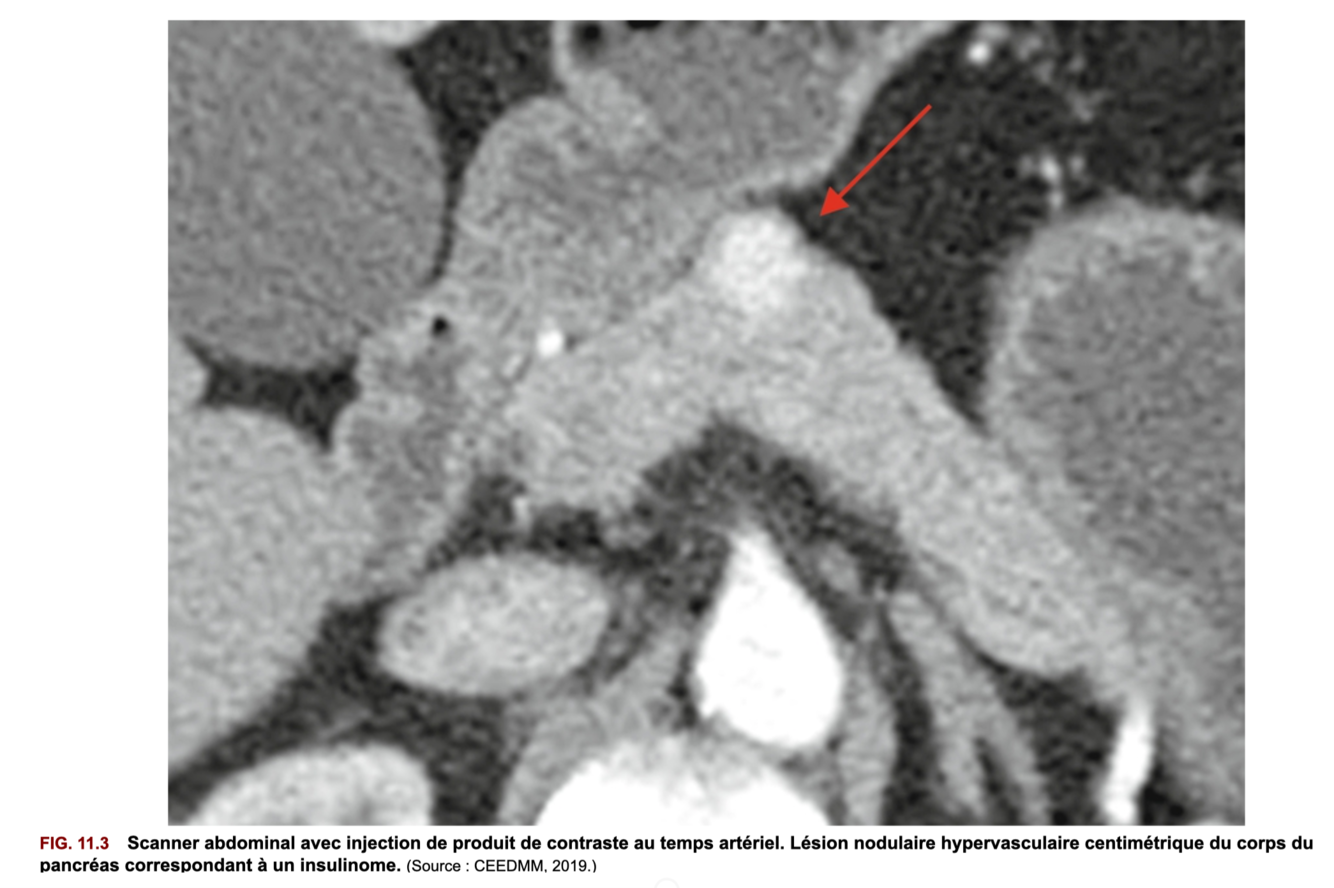

CAT après diagnostic d’un insulinome pour le diagnostic topographique :

+ IRM pancréatique si insulinome non visible sur les 2 autres examens.

=> Figure 11.3 + 11.4